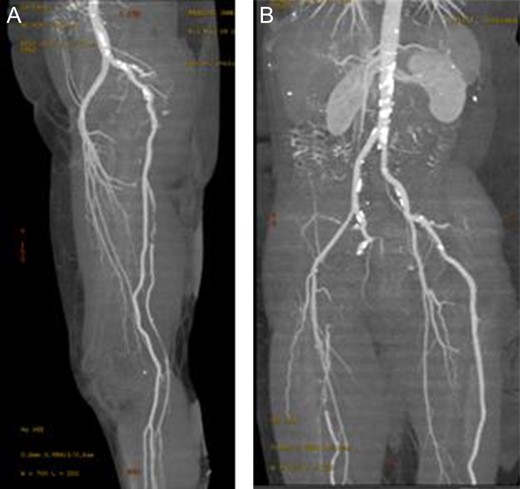

In anticipation of arterial occlusive disease, an urgent CT angiogram of the aorta and lower extremities was performed with unexpected results. Bilateral sciatic arteries supplying the popliteal arteries were identified (Figs 2A and 3A). Native bilateral superficial femoral arteries were present but small in comparison. The right sciatic artery was occluded at the sciatic notch (Figs 2B and 3B) with reconstitution of the artery within the mid thigh. Distal to this, the posterior tibial and peroneal arteries were patent. The proximal anterior tibial artery was patent, but distally occluded. There was no stenosis or occlusion on the left, with three-vessel run off below the knee.

Enhanced three-dimensionally reconstructed computed tomography angiogram, showing (A) the internal iliac artery continuing as the sciatic artery and popliteal artery bilaterally, with hypoplastic superficial femoral arteries supplying the upper thigh. The angiogram also demonstrates (B) the occlusion in the right sciatic artery at the sciatic notch, with reconstitution in the distal thigh).